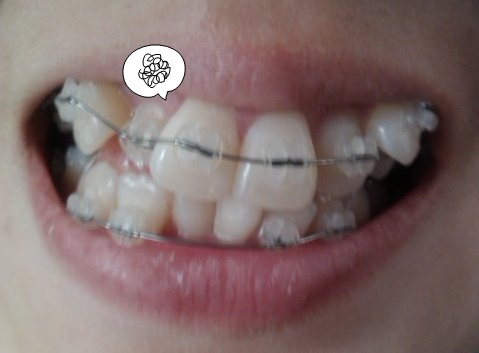

[+31] 추석부터 윗쪽 철사가 자꾸 잇몸을 찌르기에, 왁스룰 붙여가며 참다가 병원을 갓어요 철사를 똑바로 해주시고는 온김에 곰 고무줄을 챙겨 주셨어요, 덧니를 빨리 움직이게 하자고 하더라구요 사진을 보시면 아...